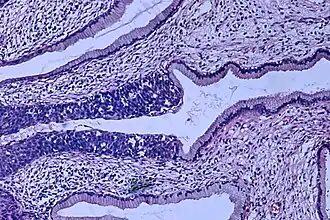

Imagen histopatológica (tinción H&E) de un carcinoma in situ, estadio 0. | ||

- CIN III: El epitelio es displásico en su totalidad. También recibe el nombre de "carcinoma in situ". La mayoría no regresan espontáneamente, y a los 2 años el 10% se ha transformado en un carcinoma invasor.